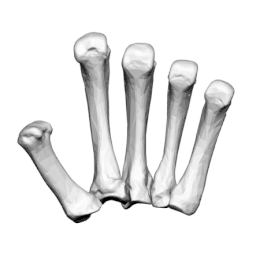

Les métacarpiens sont cinq petits os longs numérotés de 1 à 5, de dehors en dedans en position anatomique : 1 correspond au pouce et 5 à l'auriculaire. Chacun se compose d'une base proximale, d'un corps et d'une tête distale.

Os métacarpiens, vue médiale

Os métacarpiens, vue antérieure